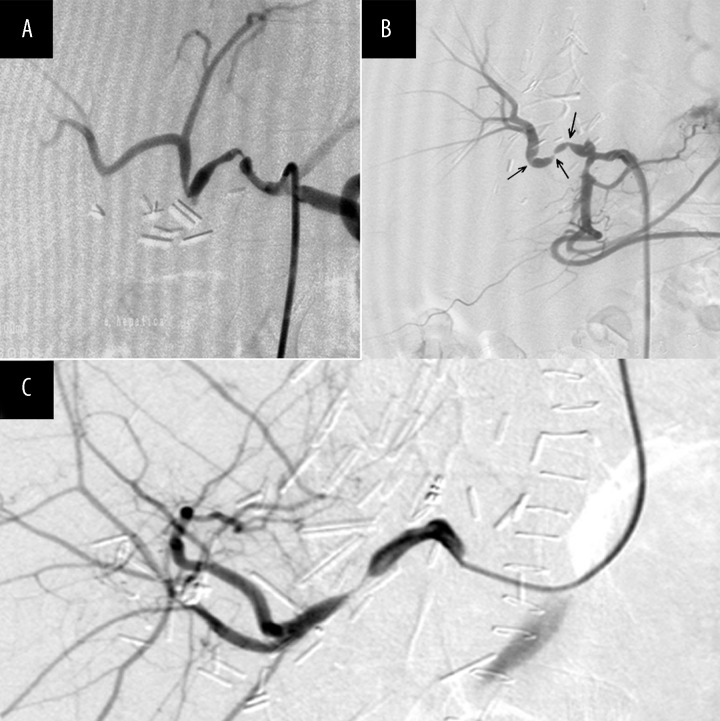

CD follow-ups were performed daily in the first week after LT, monthly after hospital discharge within the first 6 months, and in case of any blood liver test abnormalities after that period. Right and left hepatic arteries were evaluated and resistance index (RI) was calculated. Patients with abnormal CD finding were scheduled for multislice computed tomography (MSCT) angiography or digital subtraction angiography (DSA) (Figure 1). Hepatic artery stenosis was suspected when an intrahepatic Doppler waveform showed a prolonged systolic acceleration time (≥0.08 sec.) and a low RI (<0.5), and hepatic artery stenosis was confirmed by the detection of a focal peak velocity greater than 2 m/s. Early stenosis was defined as a stenosis that occurred within first 30 days after LT, and late stenosis after that period.

Figure 1.

Selective DSA of hepatic artery with two significant stenoses of the hepatic artery in the transplanted liver (A), selective DSA of hepatic artery using transfemoral approach showing three significant stenoses of the hepatic artery in the transplanted liver (B) and selective DSA of hepatic artery using a transbrachial approach, showing significant stenosis of the hepatic artery in the transplanted liver (C).